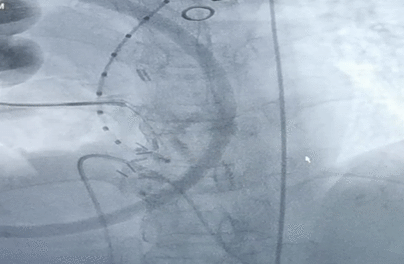

升主动脉准备:

瓣膜释放完成

在影像、超声的共同指引下,术者团队通过调整输送系统至最佳位置实现精准释放,患者跨瓣压差即刻显著下降。再行主动脉造影提示瓣膜置入位置良好、形态完整,超声提示未见明显瓣周漏。术中及术后未出现相关并发症,圆满取得此次手术成功。